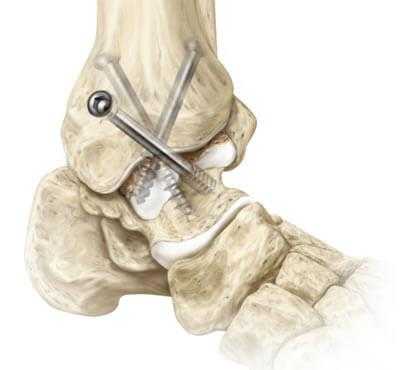

В настоящее время существует 2 основных методики проведения трансплантата через малоберцовую кость. Либо делается 2 канала диаметром соответствующие трансплантату и образующие острый угол, либо делается один канал большего диаметра в который вставляется сложенный вдвое трансплантат. При этом фиксация в малоберцовой кости в первом случае осуществляется при помощи биотенодезных винтов, во втором случае фиксация происходит за счёт титановой пуговицы. Фиксация на таранной и пяточной кости в обоих случаях идентичная при помощи биотенодезных винтов.

После подтверждения нестабильности и устранения разрастаний синовиальной и рубцовой ткани переходим к этапу забора аутотрансплантата и его подготовки к последующей трансплантации. У транспланатата 2 плеча, сложенная вдвое часть погружается в канал малоберцовой кости, а «рукава» фиксируются в каналах таранной и пяточной кости соответсвенно в месте прикрепления передней таранно-малоберцовой и пяточно-малоберцовой связок.

После подготовки транспланата выполняется продольный доступ в проекции апекса латеральной лодыжки, из которого выделяется передняя таранно-малоберцовая связка, чаще всего она бывает частично замещена рубцом в зоне прикрепления к малоберцовой кости, её желательно сохранить, прошить, и потом произвести аугментацию пластики её остатками, что будет способствовать скорейшему восстановлению проприорецепции, и вообще сделает такое восстановление возможным. Первый этап - проводим пуговичный фиксатор (в нашем случае Tight rope Arthrex) через канал в малоберцовой кости. Канал делается при помощи 2 канюлированных свёрел, 4 мм сверлом делается сквозной канал, для того чтобы через него могла пройти пуговица. Второе сверло соответсвует по диаметру сложенному вдвое транспланатау, обычно это 5 или 6 мм и этот канал заканчивается слепо на глубине 2 см, для жёсткой фиксации трансплантата после затягивания нитей на пуговчатом фиксаторе.